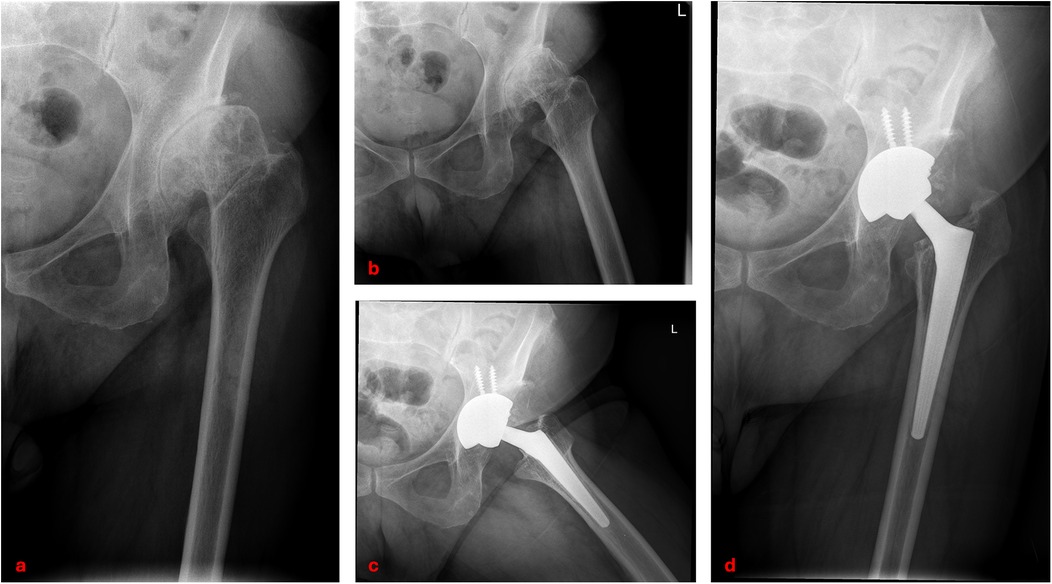

The aim of the present study was to evaluate the long-term survival, clinical outcomes, and radiographic performance of Wagner™ conical stems in patients with Crowe non-IV DDH undergoing primary THA (Figure 4).

Figure 4

X-ray images showing different views of a hip joint. Image (a) and (b) depict the hip joint before surgery, revealing bone degradation. Images (c) and (d) show the hip after joint replacement surgery, with a metal prosthesis in place.

Figure 4. Clinical case of left hip developmental dysplasia (Crowe type III): preoperative anteroposterior and lateral radiographs (a,b); postoperative radiographs at 14-year follow-up showing total hip arthroplasty with Wagner™ conical stem (c,d).